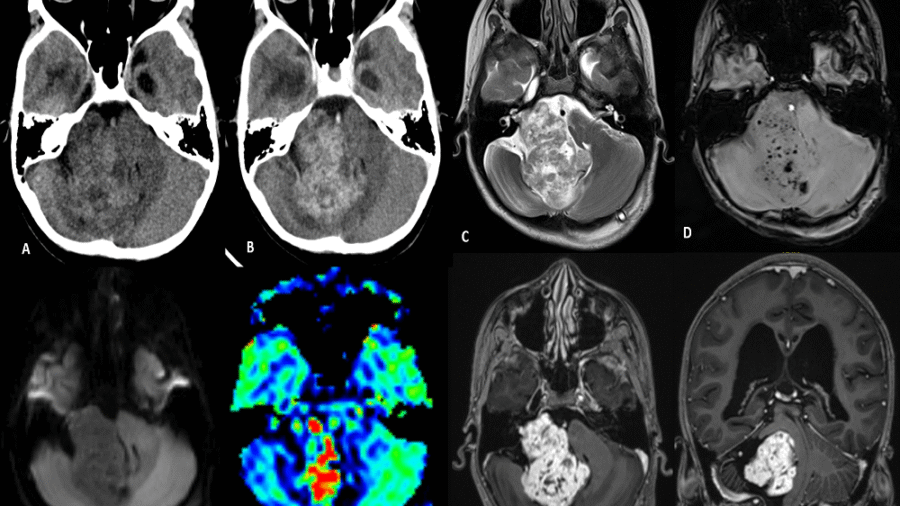

11 year old female child presented with history of right sided hearing loss, vertigo and imbalance since 6 months, right facial numbness, facial asymmetry and difficulty swallowing since 3 months, headache and vomiting since 1 month duration.